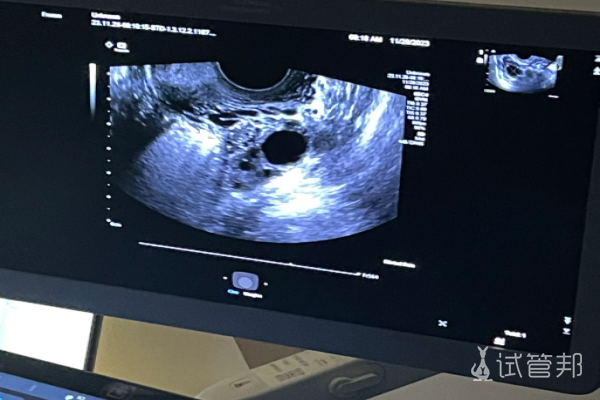

所以我在周六下午又急忙赶往医院请医生帮我检查卵泡是否已经排出。经过B超检查,医生告知我卵泡还未排出,我这才放下心来。当天晚上我和我的丈夫都因为紧张而未能安稳入睡。

6号早晨,我们自行安排了同房。7号我返回医院进行了B超检查以观察卵泡是否已经排出。B超结果显示卵泡已经成功排出。